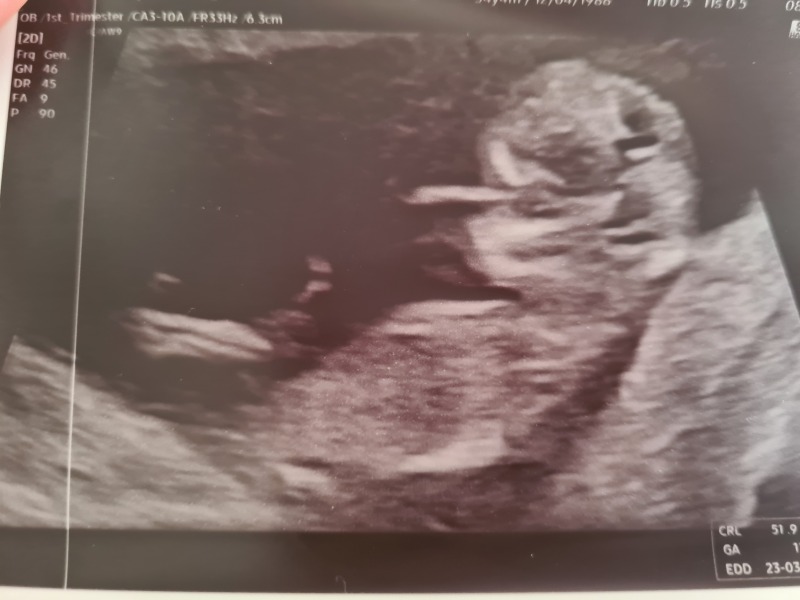

AK93 · 06/09/2022 14:17

Had my dating scan today. She said everything looked normal and pretty much measuring what was expected. Due date around 19th March. I wish the pictures were clearer as it’s not really worth sharing (my fault for being too fat 😆) but sooo happy to know there is definitely a little baby in there with a heartbeat! I hope those who also had scans today have positive news too ❤xxx

Scan this morning, measured at 11+6 but very awkward baby so not 100% and couldn't do the measurements they needed so back next week for a rescan!